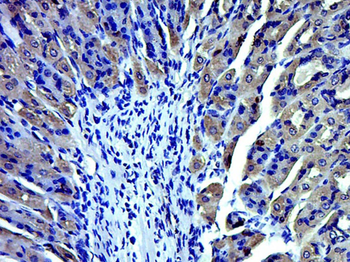

Immunohistochemical staining of human colon cancer using TRPV1 antibody